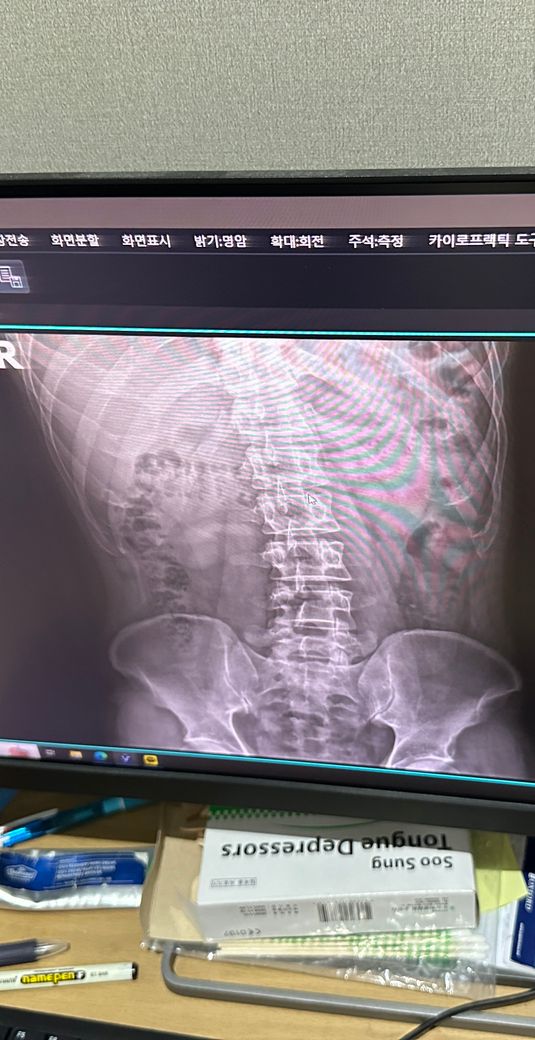

사진은 증상 생기기 일주일정도 전에 정형외과에서 찍은 사진입니다

• 4번 째 사진

엑스레이 사진을 다각도로 봐야겠지만 이 사진으로만 보기에는 흉추측만증이 있으신것 같네요 그로인해 옆구리 통증이 올수 있습니다